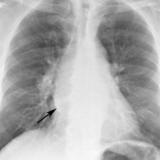

Bronch Cyst 1

arrow